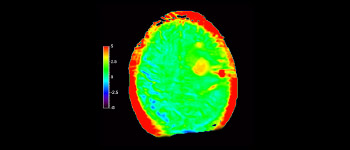

3D APT (Amide Proton Transfer) is a unique, contrast-free, brain MR imaging method addressing the need for more confident diagnosis in neuro oncology. 3D APT uses the presence of endogenous cellular proteins, to produce an MR signal that directly correlates with cell proliferation, a marker of tumoral activity. 3D APT can support trained medical professionals in differentiating low grade from high grade gliomas and, in differentiating tumor progression from treatment effect1.

Glioblastoma recurrence

Brain imaging for glioblastoma recurrence

with 3D APT